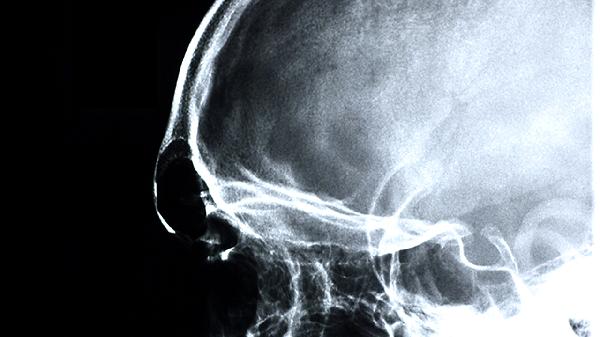

腦供血不足的用藥有什么

腦供血不足患者可遵醫(yī)囑使用阿司匹林腸溶片、阿托伐他汀鈣片、尼莫地平片、鹽酸氟桂利嗪膠囊、銀杏葉提取物片等藥物。腦供血不足可能與動(dòng)脈粥樣硬化、頸椎病、高血壓等因素有關(guān),需結(jié)合病因選擇藥物。